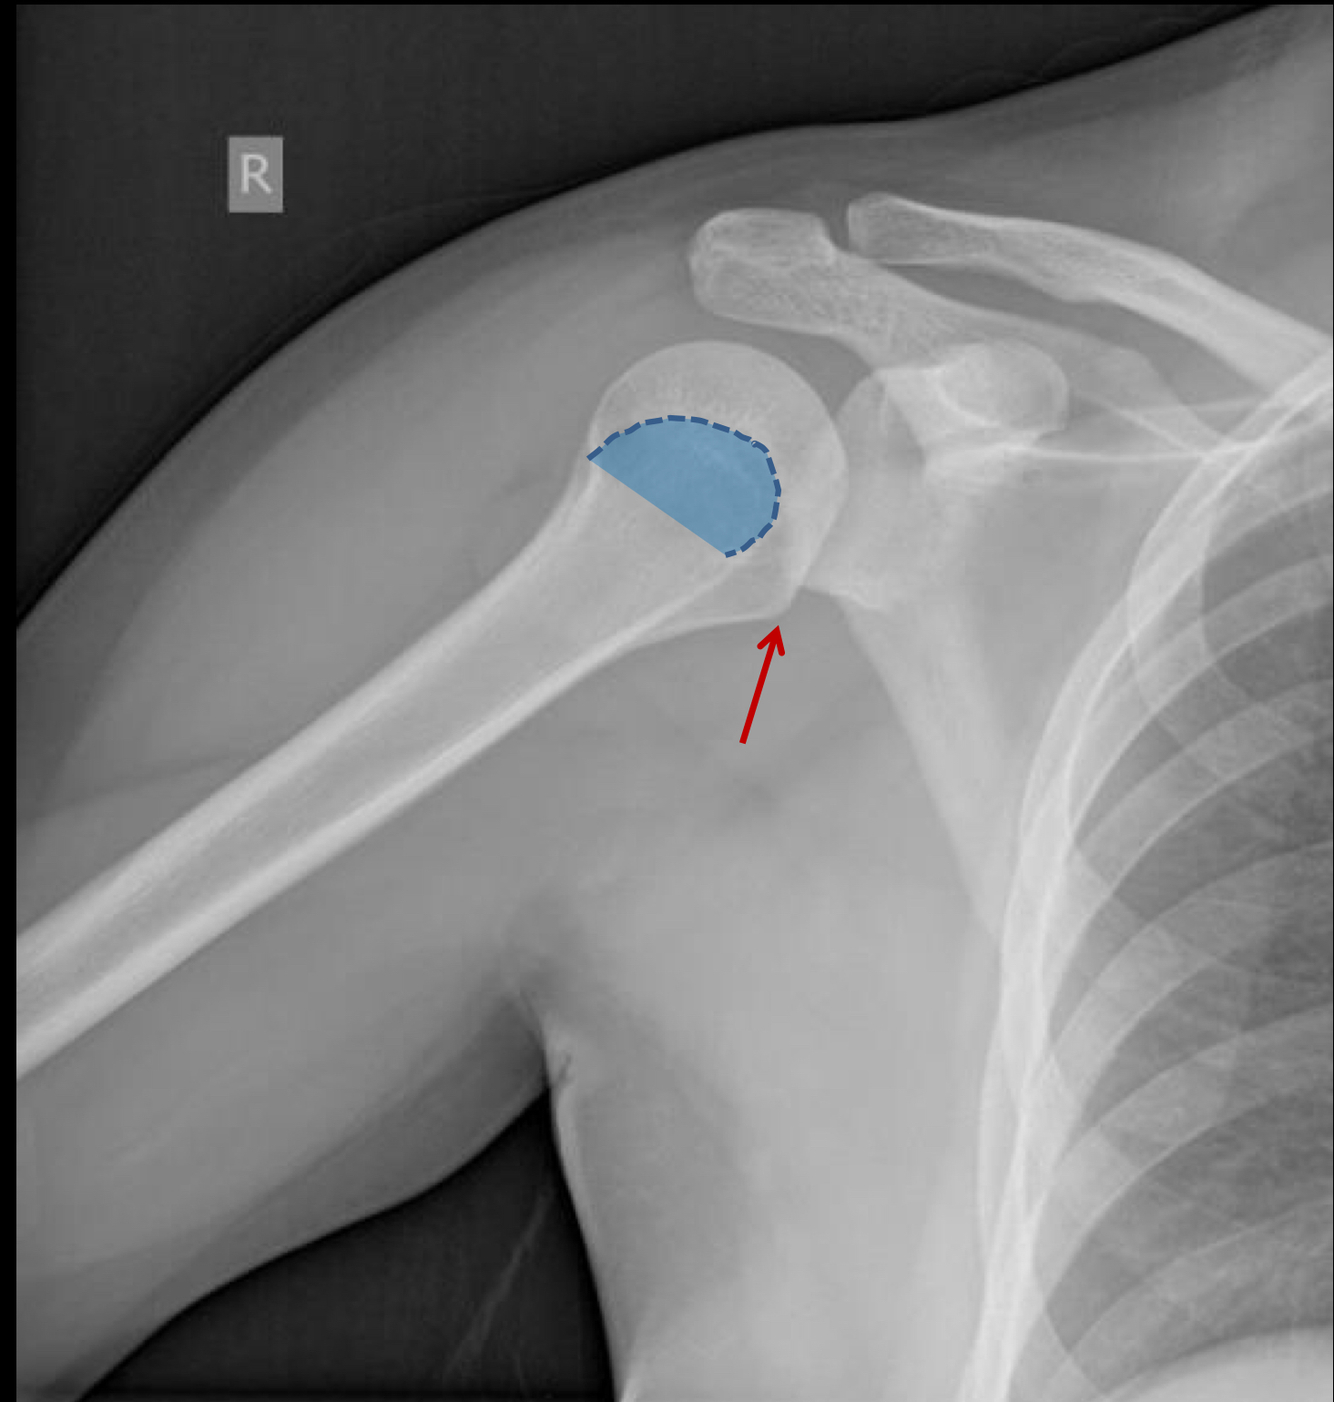

What view is this?

AP shoulder with internal rotation

What is the red arrow pointing to?

lesser tuberosity of the humerus (will be medial and in profile with internal rotation)

What is the blue area outlinging?

greater tuberosity of the humerus (will be superimposed with internal rotation)